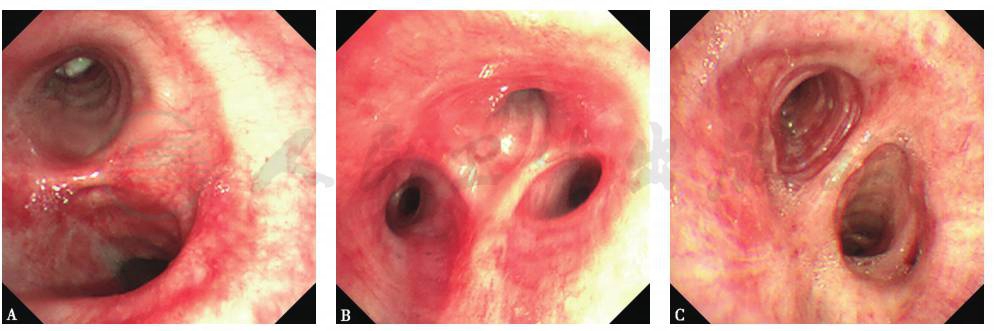

【支气管镜检查】

患者入院后,行支气管镜检查、占位性病变表面刷检涂片及活检,结果见图11~图13。

图11 支气管镜检查镜下表现

左主支气管远端见球形新生物,表面覆盖白色坏死物,管腔完全阻塞

图12 左主支气管新生物涂片

血性背景中可见少量支气管黏膜上皮细胞、散在淋巴细胞及中性粒细胞(HE染色,400×)

图13 经支气管镜左主支气管新生物活检

支气管黏膜组织慢性炎症改变(HE染色,100×)

10年前,患者左肺组织尚未完全破坏时,肺内未见结核病灶。这种情况很少见于支气管结核,且支气管镜下直视局部病变以及刷检、活检未见相关阳性证据。本病例支气管镜检查见支气管内占位性病变表面光滑,周围气道光滑,未见干酪样坏死组织,病理检查未见肉芽组织,不支持支气管结核诊断。

综合分析本病例较长的病程及支气管镜下表现、刷检和活检病理结果,目前考虑其占位性病变为良性肿瘤可能性大,进一步明确诊断须完善病变大体病理检查。另外,切除占位性病变有助于改善气道阻塞及反复感染。